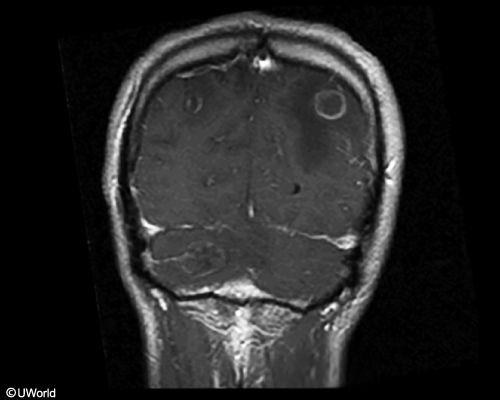

hiv+, sometimes missed prophy, 2 weeks of headaches and confusion. friends say he’s aggressive and suspicious, which is not normal for him.

toxoplasma, can reactivate if cd4 <100

could be tx/prevented with tmp-smx